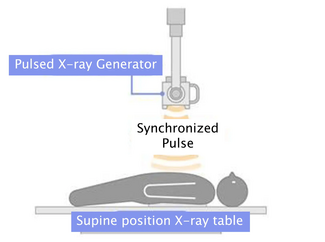

The Trellis device (Covidien) has been extensively described by our group previously.24 Briefly, it is a 6 or 8 Fr device that allows delivery of t-PA within a specific treatment zone separated from the systemic circulation by 2 balloons. A central wire allows mechanical dispersion of the t-PA within the allocated treatment zone. When a clot is deemed to be the cause of the SVC obstruction, removing it using the Trellis device without systemic intravenous thrombolytic therapy decreases the risk of hematoma, gastrointestinal bleeding, hematemesis, epistaxis, and decreases the length of hospitalization with all the associated cost and comorbidities.

Despite the fact that IPMT followed by stent placement to treat SVC thrombus has been previously described25 with good success, this article stresses the fact that the Trellis device could be used with percutaneous angioplasty without the need for stent deployment as long as there is adequate flow restoration across the stenosis. The latter strategy not only dramatically curtails the cost but also has the potential to decrease the amount of foreign thrombotic material placed in the vessel in patients where symptomatic relief is usually the primary goal. This should also decrease the complication rate that could arise from percutaneous stent placement especially those related to the stent itself such as migration, rethrombosis, SVC rupture, pacemaker lead, and/or indwelling catheter entrapment. In addition, balloon angioplasty for treatment of SVC syndrome has resulted in excellent long-term (more than 6 months) outcomes in almost all reported cases23,26-28 and should be the primary therapy of choice following IPMT in cases of SVC thrombus. However, we do agree with O’Sullivan et al25 that stent placement following IPMT should still be advocated but we think that it should be reserved to patients who fail IPMT and balloon angioplasty and those without indwelling venous lines or pacemaker leads.

Therefore, we recommend following a staged procedural strategy for treatment of SVC thrombus (Diagram 1). When patients present with SVC thrombus, IPMT should be attempted first (Step 1), followed by balloon angioplasty (Step 2), and then stenting (Step 3), depending on the ultimate results. We define “good result” as less than 30% stenosis seen on the follow-up venogram with less than 5 mm Hg of pressure gradient along with restoration of the respiratory variation in the distal segment. If the repeat angiogram and pressure calculation reveal a good result at any step, the procedure can be aborted with adequate outpatient follow-up in 1 month.